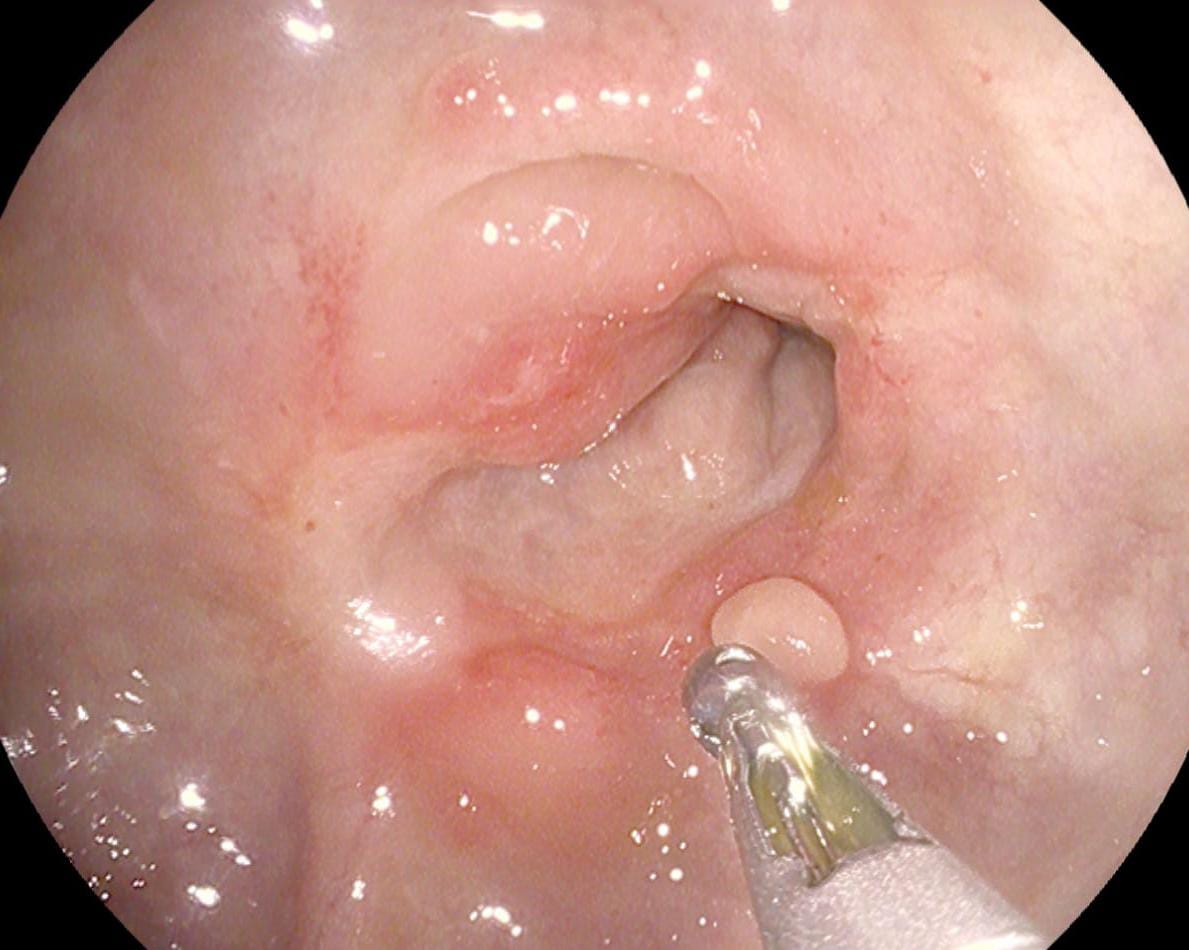

استقبل قسم مناظير الكبد والجهاز الهضمي بمستشفى أبو كبير المركزي طفل يبلغ من العمر 5 سنوات، يعاني من صعوبة في البلع والتنفس؛ نتيجة ابتلاع عملة معدنية أدت إلى انسداد مجرى الطعام.

على الفور تم التحضير لمنظار علوي طوارئ، وقام الفريق الطبي بقسم المناظير بمشاركة الدكتور عبدالمنعم زناتي، والدكتور صهيب إبراهيم، والدكتور عبدالستار محمد، والدكتور أسماء رزق، بالإضافة للدكتورة أسماء السيد استشاري التخدير، باستخراج العملة المعدنية من مرئ الطفل، وتم خروج الحالة من المستشفى بصحة جيدة.